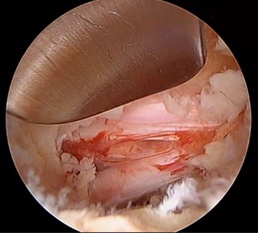

Spinal surgeries can have varied results, sometimes leading to more pain, long recovery times, and severe side effects. Lawless introduced another option for patients: a minimally invasive endoscopic procedure. This is becoming a routine procedure that relieves pinched-nerve sciatica resulting from spinal decompression.

The endoscope allows the physician to be more precise than in a more invasive open surgery. The department already has an endoscope, so there is little to no extra cost. The surgery also provided additional training for the hospital corpsman assigned to neurosurgery. Petty Officer 3rd Class Alyssa Clayton was able to scrub in and assist Dr. Lawless during the procedure.

While at the hospital, Lawless performed the first endoscopic laminectomy on the island. A laminectomy is a surgical procedure that removes a portion of the bony roof of the spine, called the lamina, to relieve pressure on the spinal cord or nerves. The patient had an excellent result with immediate relief of leg pain and did not require any narcotic pain medication.

This surgery has the same benefits as an endoscopic microdiscectomy: smaller incisions, less trauma to muscle and soft tissues resulting in less postoperative pain, and fewer complications and infections. This allows the procedure to be performed in an outpatient setting so patients can go home the same day.